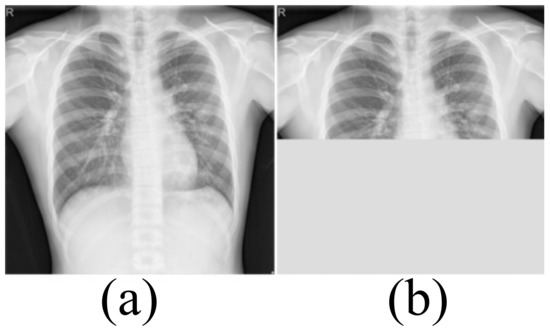

3.1. Dataset

Data Enhancement